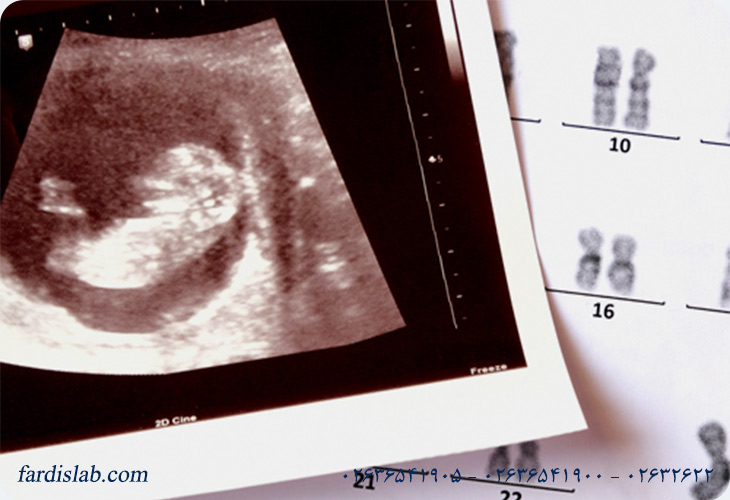

غربالگری سه ماهه اول بارداری به مجموعهای از ارزیابیها گفته میشود که در اوایل دوران بارداری(معمولاً بین هفتههای ۱۰ تا ۱۴ بارداری) انجام میشود تا احتمال وجود برخی ناهنجاریهای کروموزومی در جنین سنجیده شود. این ناهنجاریها شامل سندروم داون(Trisomy ۲۱)، سندروم ادوارد(Trisomy ۱۸) و سندروم پاتو(Trisomy ۱۳) هستند، که میتوانند سلامت و رشد کودک را بهصورت قابل توجهی تحت تاثیر قرار دهند.

این غربالگری بهعنوان بخشی از مراقبتهای پیش از زایمان طراحی شده تا اطلاعات حیاتی درباره سلامت جنین در اختیار والدین قرار دهد. برخلاف تستهای تشخیصی که نتیجه قطعی میدهند، این ارزیابی ریسک یک وضعیت را مشخص میکند و کمک میکند که اگر احتمال خطر بالاست، اقدامات بعدی مانند تستهای تشخیصی دقیقتر CVS یا آمنیوسنتزانجام شوند.

یکی از کلیدیترین اجزای غربالگری سه ماهه اول بارداری، اندازهگیری مارکرهای بیوشیمیایی در خون مادر است. این مارکرها اساس علمی غربالگری را تشکیل میدهند و در کنار سن مادر و سونوگرافی NT کمک میکنند تا با دقت بیشتری ریسک ناهنجاریهای کروموزومی مانند سندروم داون، تریزومی ۱۸ و تریزومی ۱۳ پیشبینی شود. دو مارکر اصلی که در این آزمایش خون اندازهگیری میشوند عبارتاند از:

این پروتئین توسط جفت ساخته میشود و سطح آن در دوران بارداری تغییر میکند. در غربالگری سه ماهه اول، سطح PAPP‑A در خون مادر بررسی میشود و کاهش غیرطبیعی آن با افزایش احتمال ناهنجاریهای کروموزومی مرتبط است، بهخصوص سندروم داون.

این هورمون نیز توسط جفت تولید میشود و نقش مهمی در تنظیم بارداری دارد. در شرایطی که غربالگری سه ماهه اول انجام میشود، مقادیر Free β‑hCG بهطور نسبی افزایش یا کاهش مییابد و الگوی آن میتواند نشانه ریسک سندروم داون یا دیگر اختلالات باشد. مثلاً در تریزومی ۲۱ این مقدار تمایل دارد بالاتر از حد طبیعی باشد، اما در تریزومیهای دیگر ممکن است کاهش یابد. حسگرهای این دو مارکر وقتی با سن مادر و نتایج سونوگرافی NT تلفیق میشوند، یک مدل ریسک تولید میکنند. این مدل به پزشکان اجازه میدهد تا احتمال اختلال کروموزومی در جنین را بهصورت کمی تخمین بزنند مثلاً اینکه احتمال ابتلا یک جنین به سندروم داون ۱ در ۱۰۰۰ باشد یا ۱ در ۱۰۰.